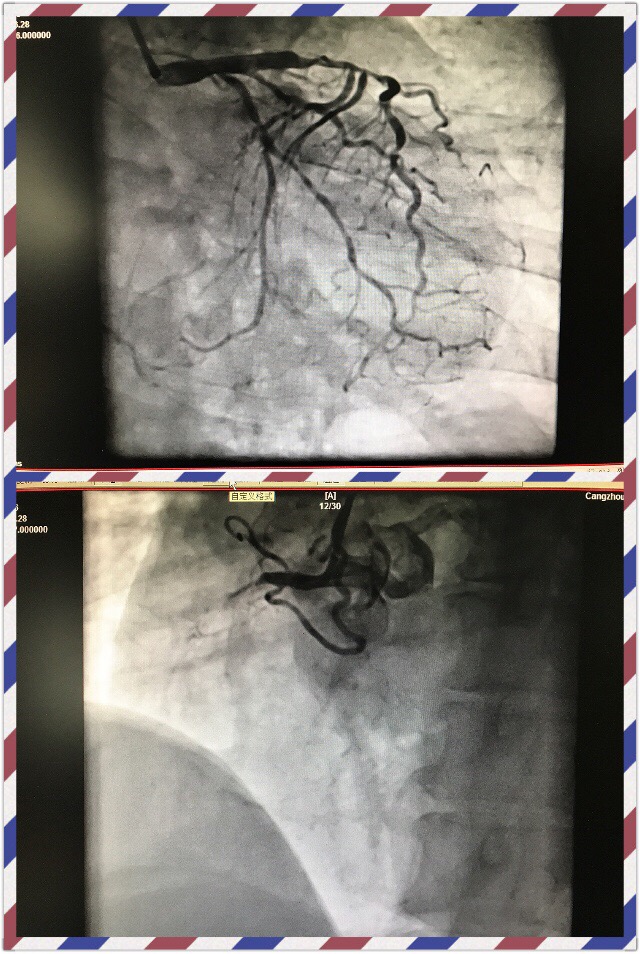

首先我想分享三个我们亲自经历的病友的故事。第一例,是我多年的朋友,并且还有几个共同的好友,45岁男性,已经有多次严重心绞痛症状,但听说"支架"不良传说,极其排斥支架,多次劝说后同意冠脉造影看看有多严重。造影发现前降支有近乎闭塞的局限病变。出现心梗的风险极高,非常适宜支架植入术。手术台上我们花了很长时间说服并且以朋友的名义担保。才接收了介入治疗。2年过去了,他才彻底消去疑虑。

第二例更加令人痛心,从河北农村来的66女性,有过脑梗史,因严重心绞痛转入我科,每步行十余步或上厕所就发作胸闷,一入院就一级护理,积极术前准备,两天后列入手术记划,但患者觉得自己″好多了",要先回家照顾老伴,顺便再凑点钱。无论如何劝说交待她的危险都不接收,因考虑到患者有可能转其医院手术,把方案详细交待后出院。悲哀的是第二天下午传来消,患者由于心梗死于家里。生命就这样在马上到岸时侯重返大海翻船。